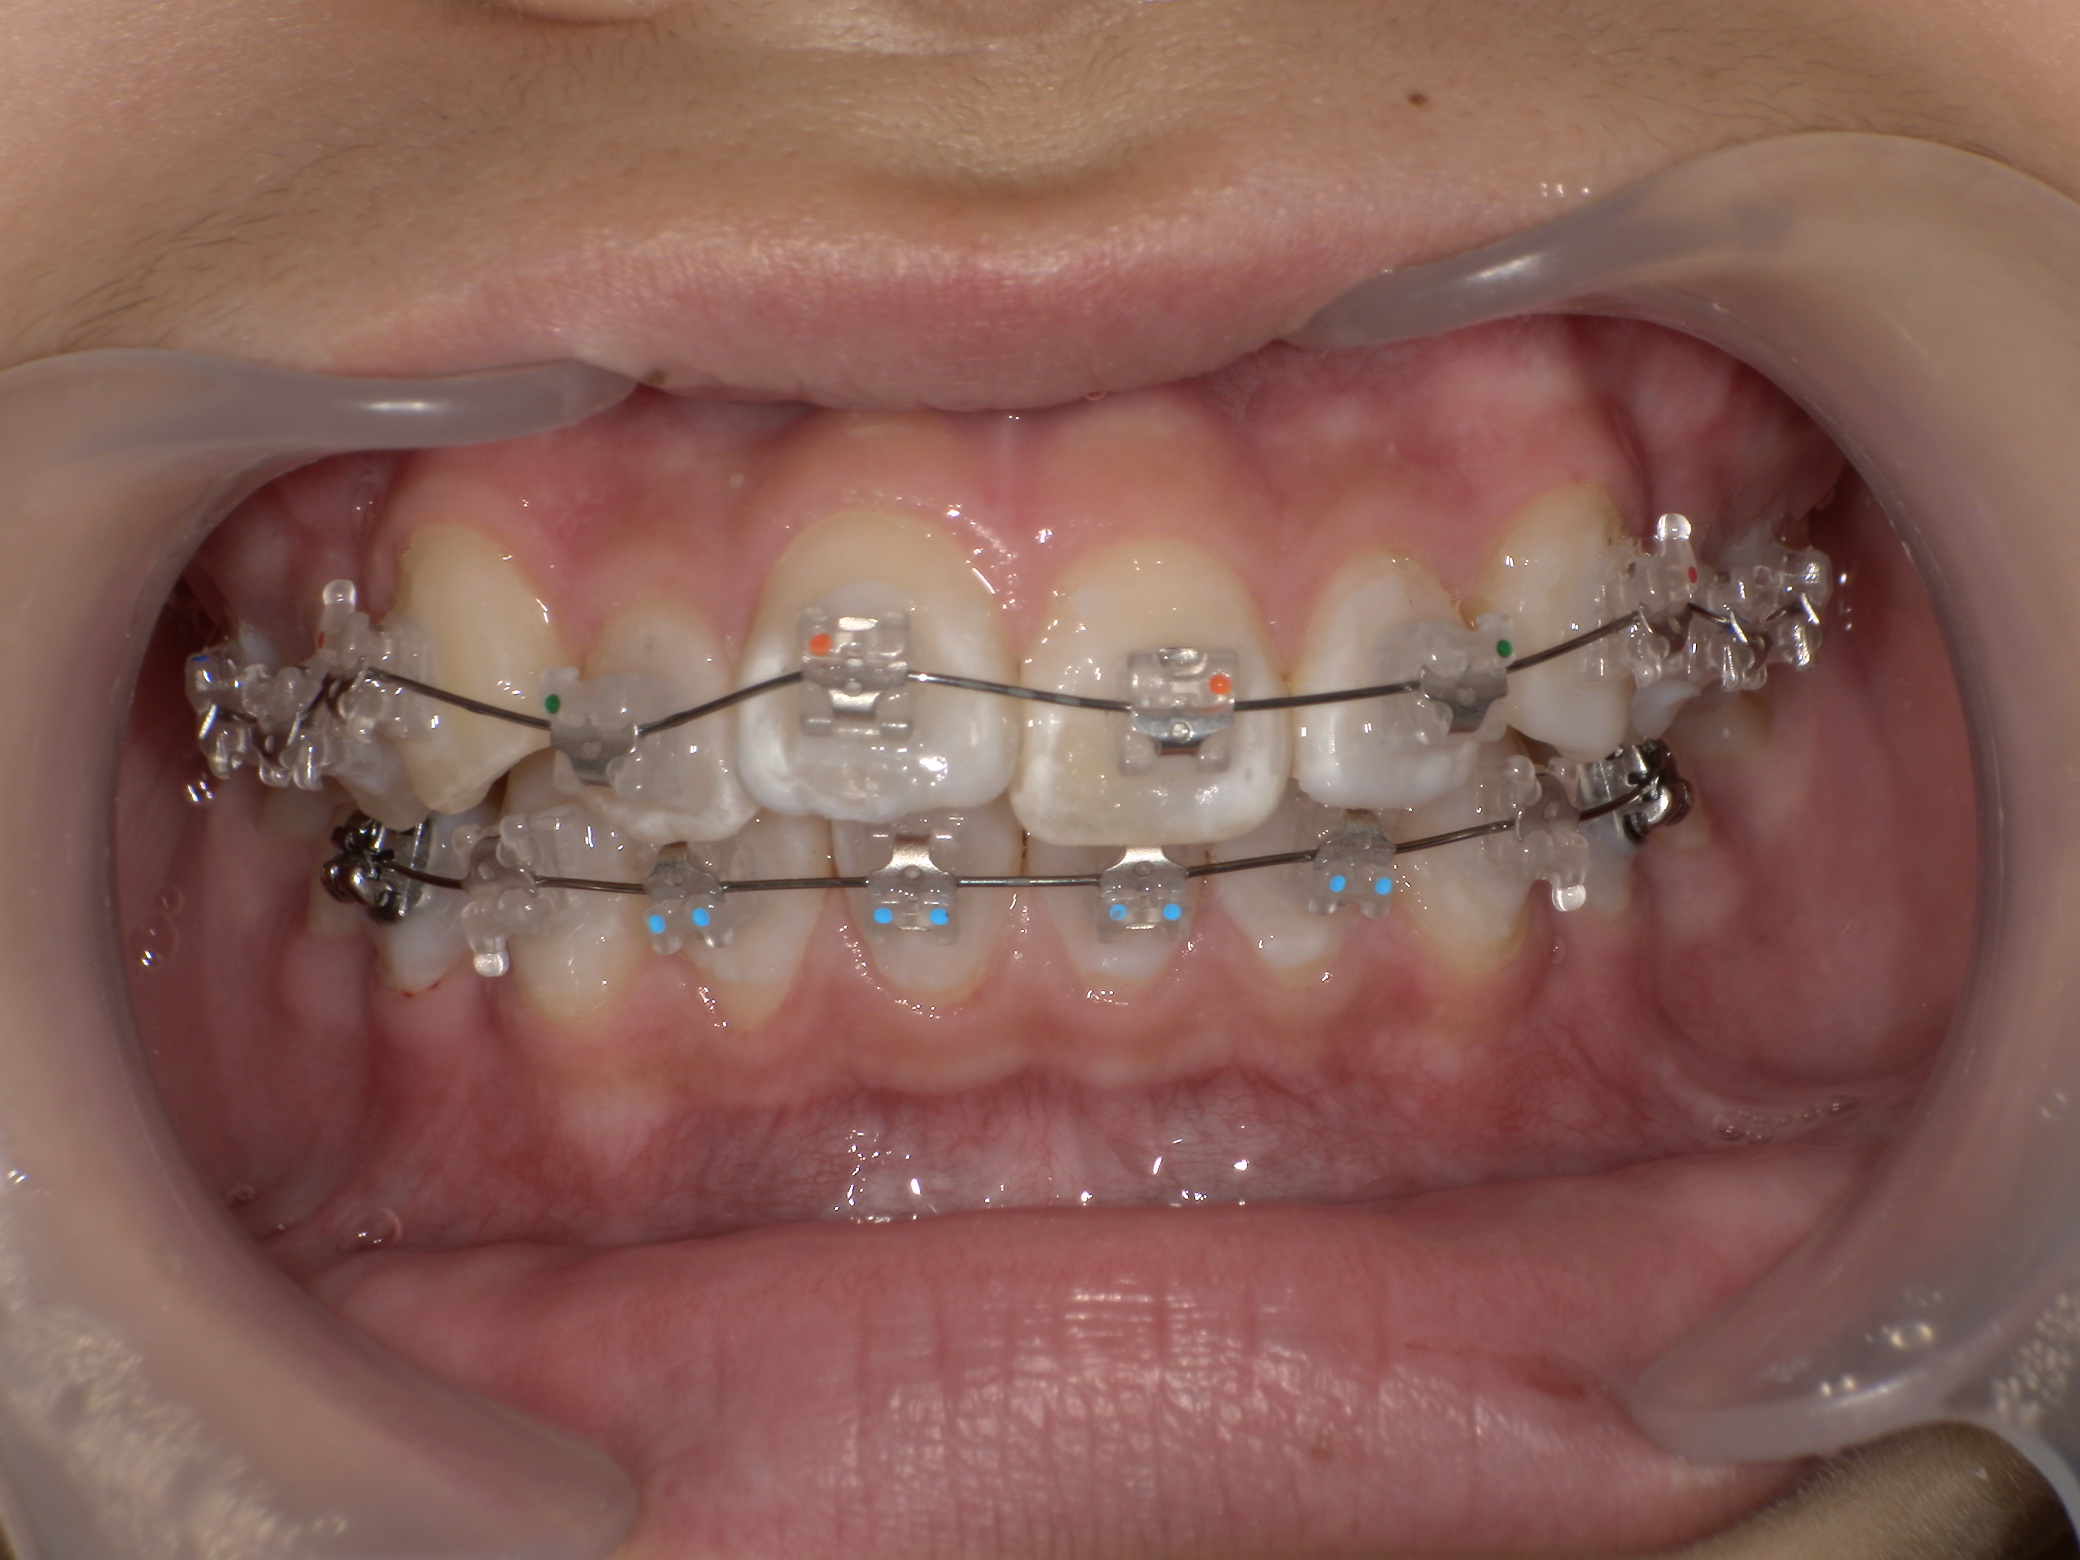

部分矯正症例|左の奥歯がかみ合っていない(シザーズバイト)

2026/03/19 小児矯正